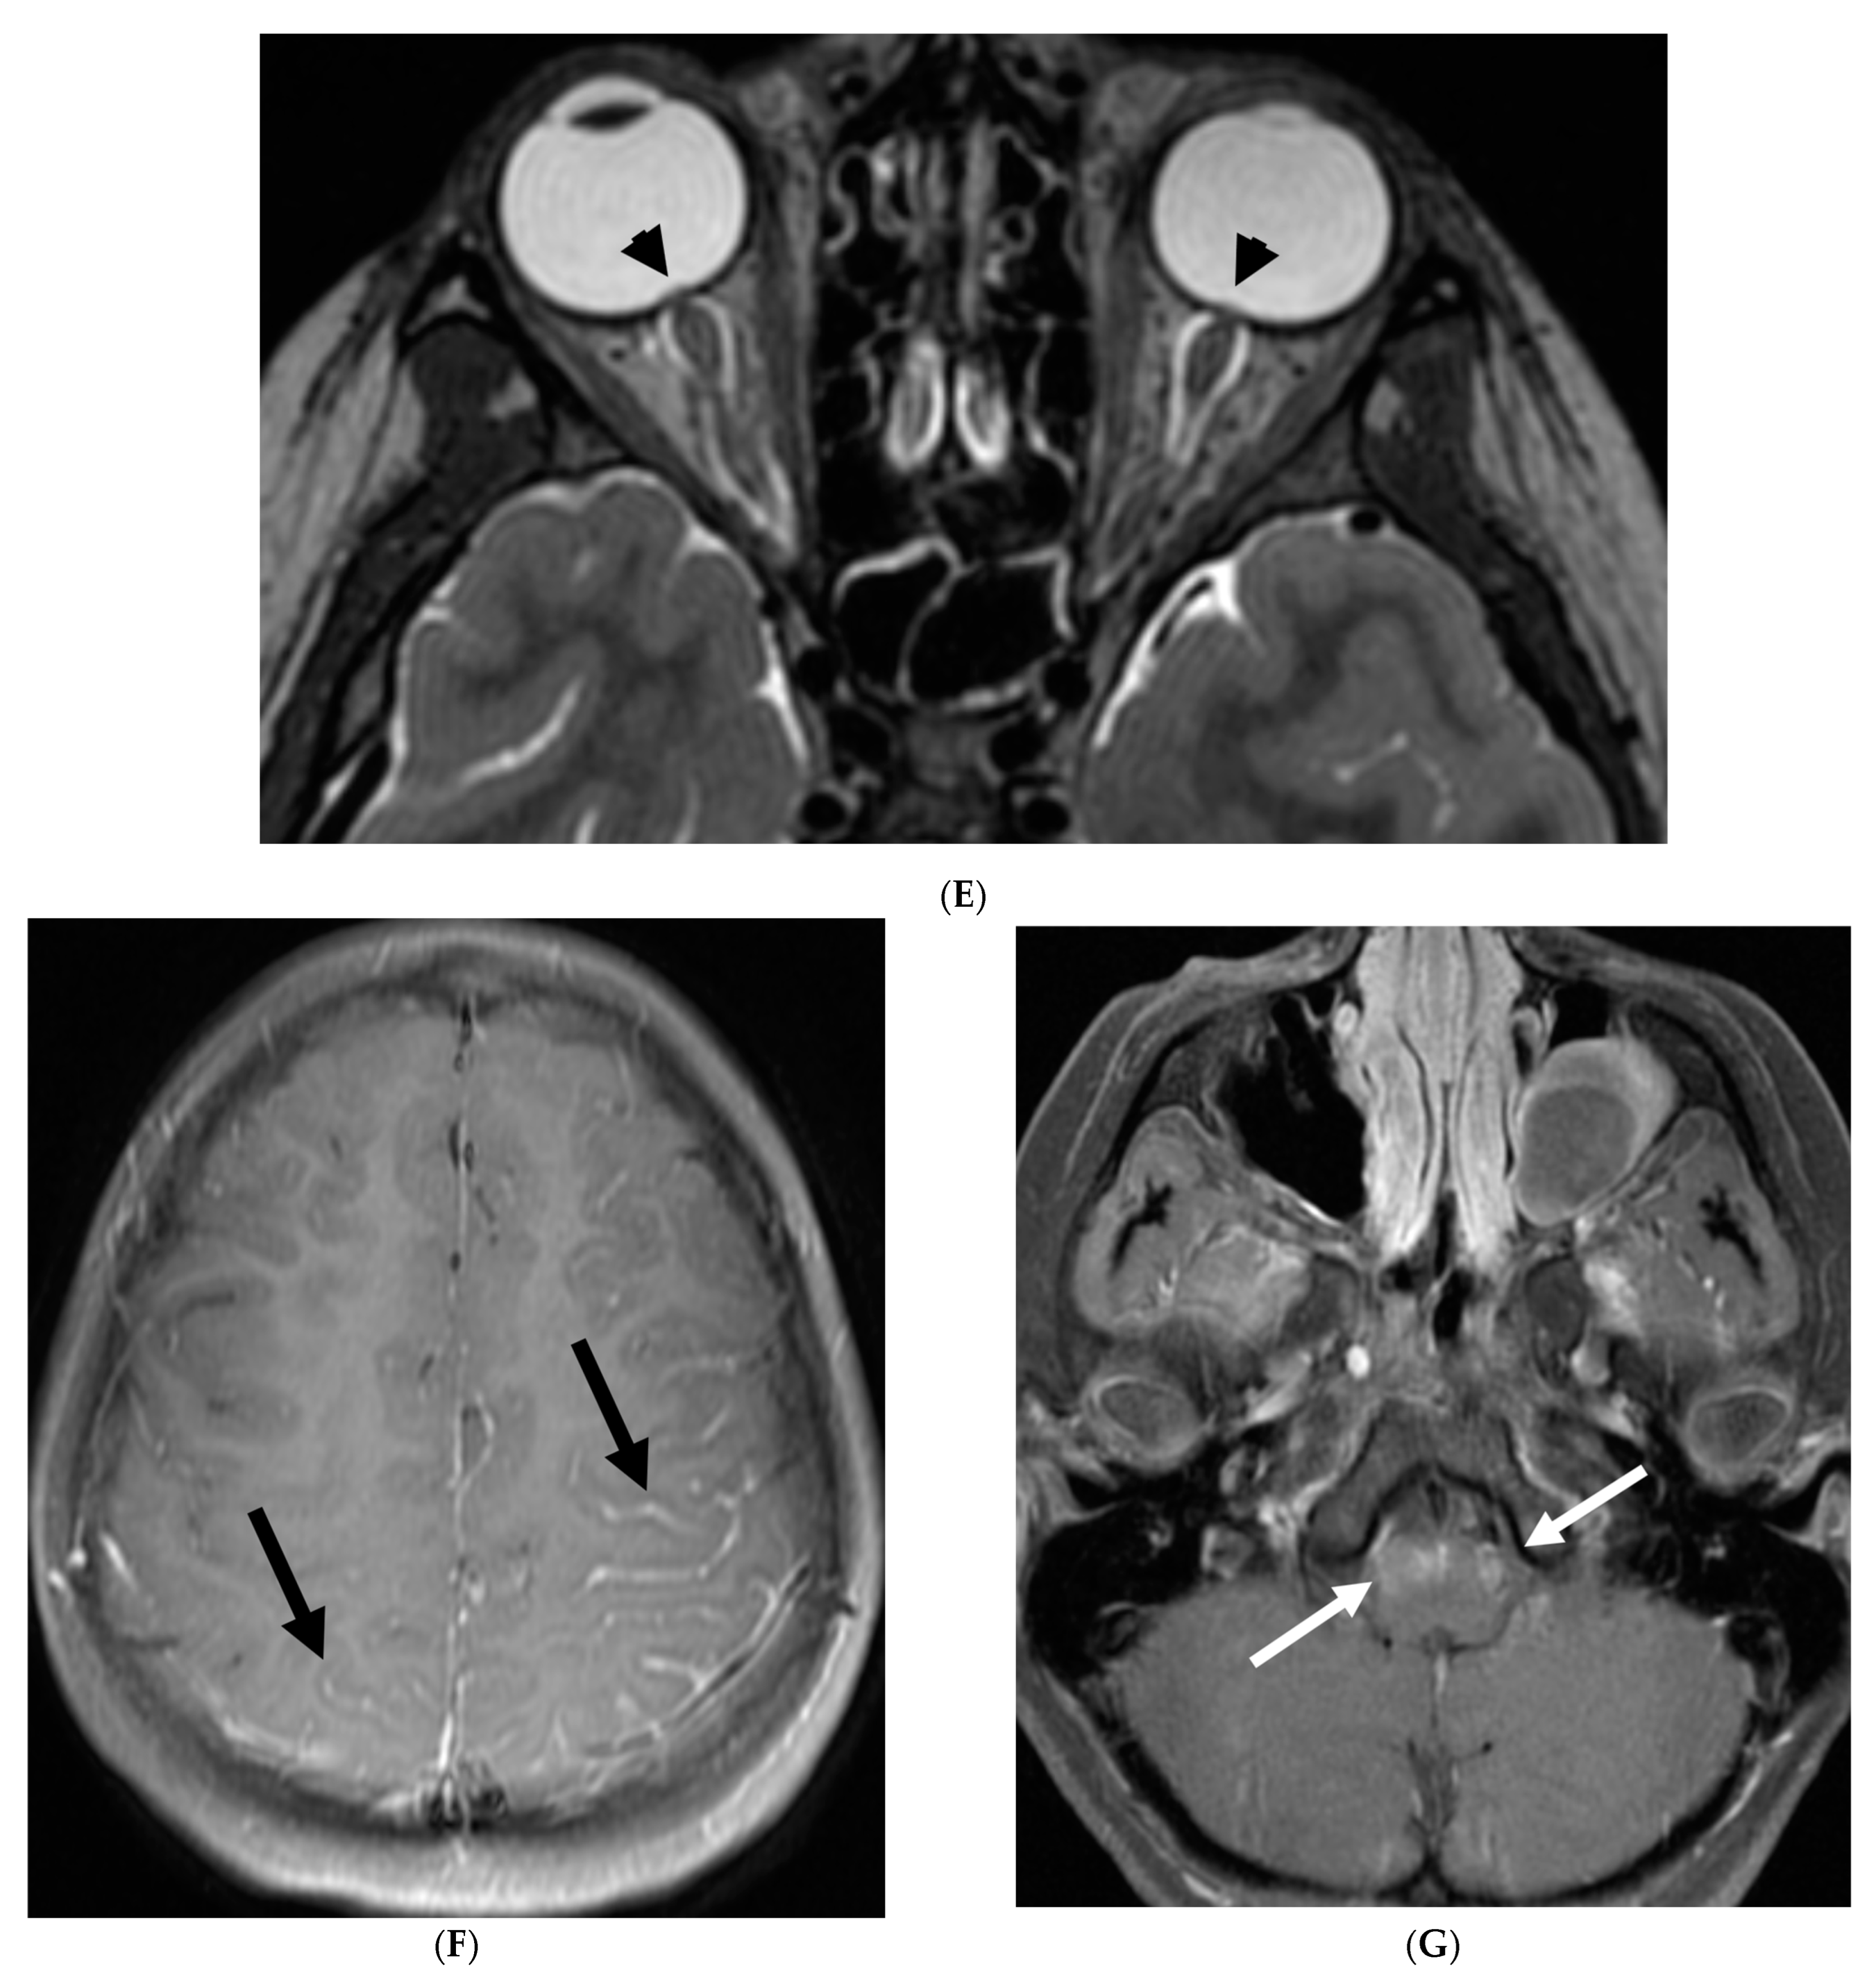

5.3. Anti-Myelin Oligodendrocyte Glycoprotein (MOG) Demyelination

Anti-MOG antibody associated demyelination (MOGAD) frequently presents as Acute Disseminated Encephalomyelitis (ADEM) in children and opticospinal involvement in young adults [105]. Bilateral but asymmetric T2 hyperintense lesions occur in thalamus, pons and cerebellar peduncles are common in children [106]. Optic nerve involvement typically presents as a long segment with anterior predominance, in contrast to the posterior predominance seen in Neuromyelitis Optica Spectrum Disorders (NMOSD) and the short segment involvement characteristic of Multiple Sclerosis (MS) [106].

LME has been shown to present early in the disease course and is much more common in children (33%) compared to adults (8%) [107]. Gadde et al. found that 8% of pediatric MOG antibody-associated demyelination cases had only LME without any other central nervous system manifestation. LME when present can be particularly helpful in differentiating from NMOSD [106]. Furthermore, Valencia-Sanchez et al. reported a significant association between LME and cerebral cortical encephalitis in MOG antibody-associated disease. This finding suggests that LME may be an important marker for cortical involvement and potentially more severe disease (Figure 21) [108].

Figure 21.

Sagittal T2 (A,B), axial FLAIR (C), axial T2 cervical spine (D) at the level of C7 vertebral body and Axial T2 orbits (E): 12-year-old girl presented with right focal motor seizure and left temporal lobe slowing on electroencephalogram (EEG). Right eye vision loss and irritability. Ill-defined areas of signal abnormalities are identified within the RIGHT mesial temporal lobe and bilateral medulla (white arrows). FLAIR hyperintensity is identified on the left central sulcus (black arrow). Small focus of signal abnormality is seen on the right side of the cord at the 7th cervical vertebra (C7) (dashed arrow). There is also bilateral papilledema (arrowheads). Post contrast axial T1 (F,G), axial T1 orbits (H) and axial T1 cervical spine at C7 (I): Asymmetric LME (black arrows) predominantly involving the left cerebral hemisphere, with minimal right parietal involvement is seen. Ill-defined enhancement in the right mesial temporal lobe, and right greater than left medulla (white arrows) corresponds to the signal abnormality. There is right greater than left, optic nerve enhancement (curved arrow). Single small enhancing lesion in the spinal cord on the right at the level of C7 corresponds to the signal abnormality (dashed arrow). Features favor a demyelinating process. MOG antibodies were positive at 1:20 in keeping with Myelin oligodendrocyte glycoprotein (MOG) antibody disease (MOGAD).